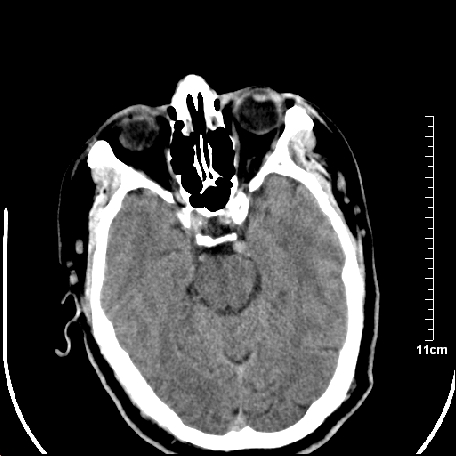

外伤患者,什么病,

外伤患者,没什么症状,

颅内未见明显创伤性影像,建议上传骨窗,看看左侧颧弓

双侧外侧裂,左侧脑沟见高密度结节影,边清,还有鞍上池层面密度也高

都是血管。

脑血管硬化?高血红蛋白症?

2.老年脑,基底动脉硬化迂曲。

基底动脉硬化迂曲。高血红蛋白血症。